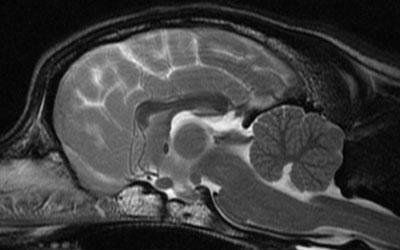

Neurologia veterinaria a vicenza

N eurologia veterinaria è una branca di medicina veterinaria specializzata nell'ambito dell' anomalie e i disturbi che colpiscono il sistema nervoso.

Sistema nervoso comprende il cervello, il midollo spinale, i nervi spinali e le giunzioni tra nervi e i muscoli.

I metodi diagnostici utilizzati dai neurologi veterinari comprendono

esame fisico e racolta dell'anamnesi,

valutazione radiografica (in bianco nero e con mezzo di contrasto-MIELOGRAFIA)

analisi del liquido cerebrospinale,

risonanza magnetica e TC,

test elettrodiagnostico che comprende la valutazione della velocità della conduzione nervosa.

esame di potenziali evocati uditivi-BAER.

Epilessia e malattie neuromuscolari possono avere un impatto significativo sulla salute del vostro animale e devono essere affrontati immediatamente in quanto possono presto diventare ancora più dannosi senza un trattamento. I progressi nella tecnologia hanno aiutato neurologi nella localizzazione delle lesioni neurologiche con conseguente allungamento della vita degli animali.

Un esame diagnostico completo sarà fatto per stabilire come trattare correttamente un paziente con una malattia neurologica. La prima cosa che facciamo è di stabilire se i sintomi si riferiscono ad un problema all'interno del sistema nervoso. Se i disturbi sono neurologici, andiamo a localizzarli e valutare l'entità del problema. Una volta che questo è stato determinato discuteremo le diverse opzioni di trattamento.